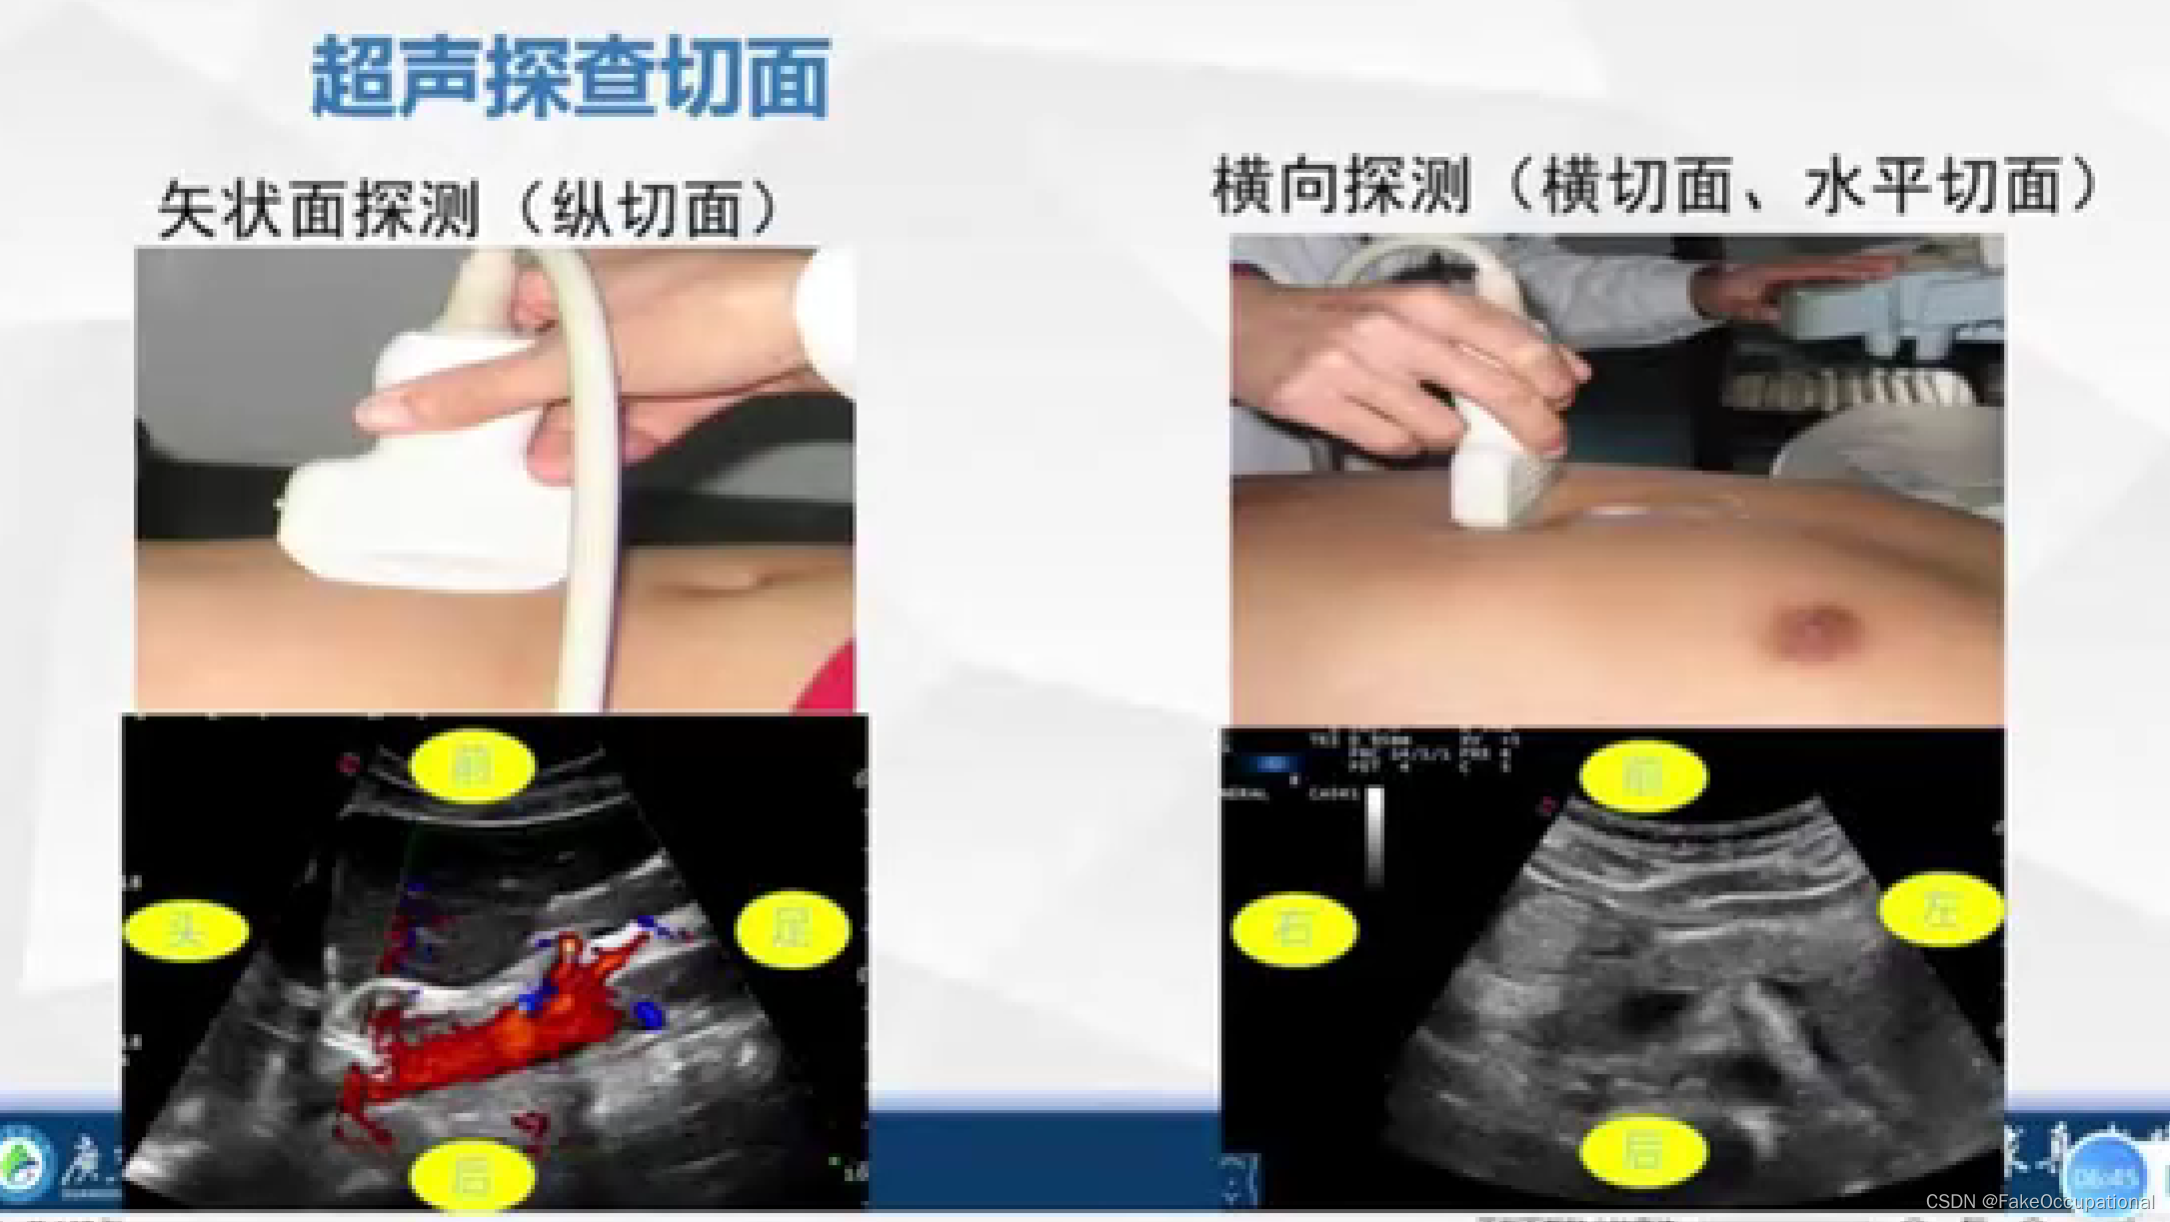

- 探头上是有方位标记点的,显示器中方位点在左侧。标准方向放置后,患者的右侧应该出现在显示器的左侧。探头一侧的探头方向标记应面向患者的右侧(如果探头纵向定向,则朝向头侧),并且超声监视器上的标记点位于超声监视器的左上角。

- 图中前后指的是深度